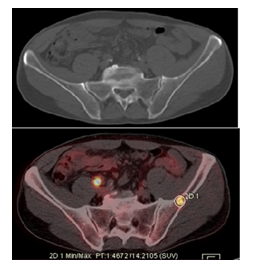

Our patient was a 65-year-old female diagnosed with Grade III ER-/PR-/Her-2 invasive ductal carcinoma in the left breast. She underwent neoadjuvant chemotherapy, followed by left mastectomy and radiotherapy. Six months after completion of therapy, the patient presented for a routine clinical evaluation and underwent a follow-up 18F-FDG PET/CT examination. At the time of referral, the patient reported mild persistent pain in the right upper limb, without a history of trauma. The laboratory tests showed normal platelet counts, hemoglobine and white blood cells, mild elevation of alkaline phosphatase. In addition, tumor marker CA 15-3 was above the normal refrence range 68U/mL, while CEA was normal. Liver and renal function test were within the normal limits. The 18F-FDG PET/CT images identified two focal areas of increased radiotracer uptake in the right iliac bone and the right femoral bone, both without noticable structural abnormalities on the CT. There were considered metabolically active but CT-negative bone lesions. Furthermore, a focal FDG-avid pulmonary lesion was detected, suspicious for lung metastases.